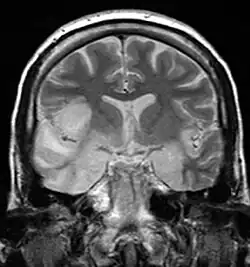

Herpesviral encephalitis and herpesviral meningitis Herpes simplex encephalitis (HSE) is a rare life-threatening condition that is thought to be caused by the transmission of HSV-1 either from the nasal cavity to the brain's temporal lobe or from a peripheral site on the face, along the trigeminal nerve axon, to the brainstem.[19][20][21][22] Despite its low incidence, HSE is the most common sporadic fatal encephalitis worldwide. HSV-2 is the most common cause of Mollaret's meningitis, a type of recurrent viral meningitis.